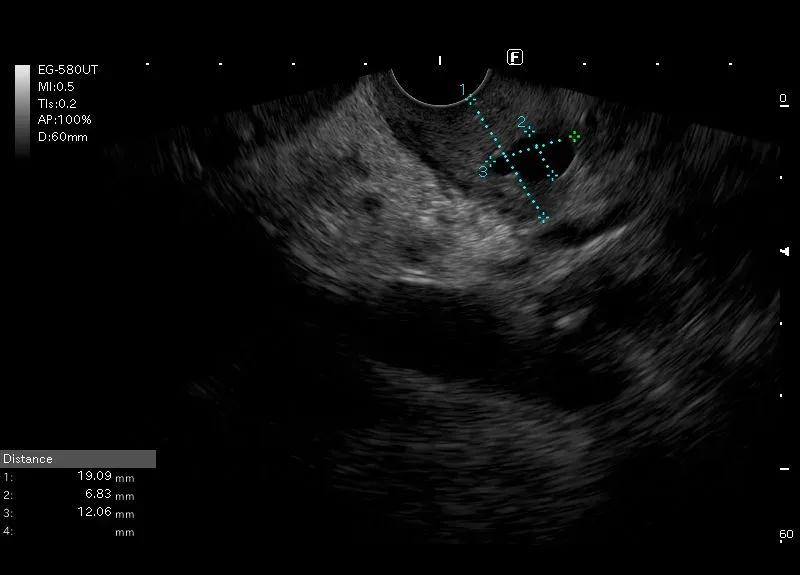

Pogrubiała ściana dwunastnicy z drobnymi torbielami w ścianie - w wybranym przypadku obraz zapalenia bruzdy.